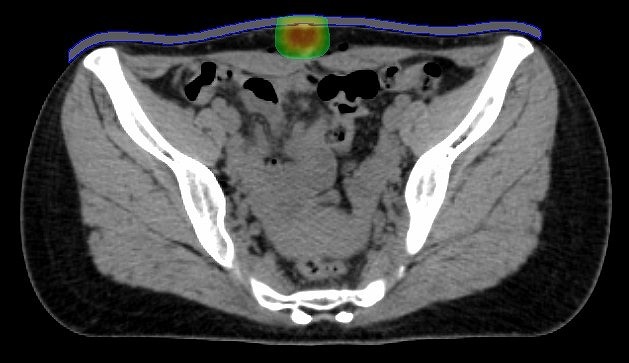

IMRTを用いて肛門がんと転移しやすいリンパ節領域に照射。